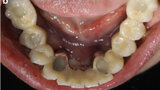

Fig. 7a: CAD/CAM model with the prefabricated titanium abutments (a), CAD/CAM cobalt–chromium framework (b) and composite veneered provisional FDP (c & d) before bonding to the abutments.

Fig. 7b: CAD/CAM model with the prefabricated titanium abutments (a), CAD/CAM cobalt–chromium framework (b) and composite veneered provisional FDP (c & d) before bonding to the abutments.

Fig. 7c: CAD/CAM model with the prefabricated titanium abutments (a), CAD/CAM cobalt–chromium framework (b) and composite veneered provisional FDP (c & d) before bonding to the abutments.

Fig. 7d: CAD/CAM model with the prefabricated titanium abutments (a), CAD/CAM cobalt–chromium framework (b) and composite veneered provisional FDP (c & d) before bonding to the abutments.